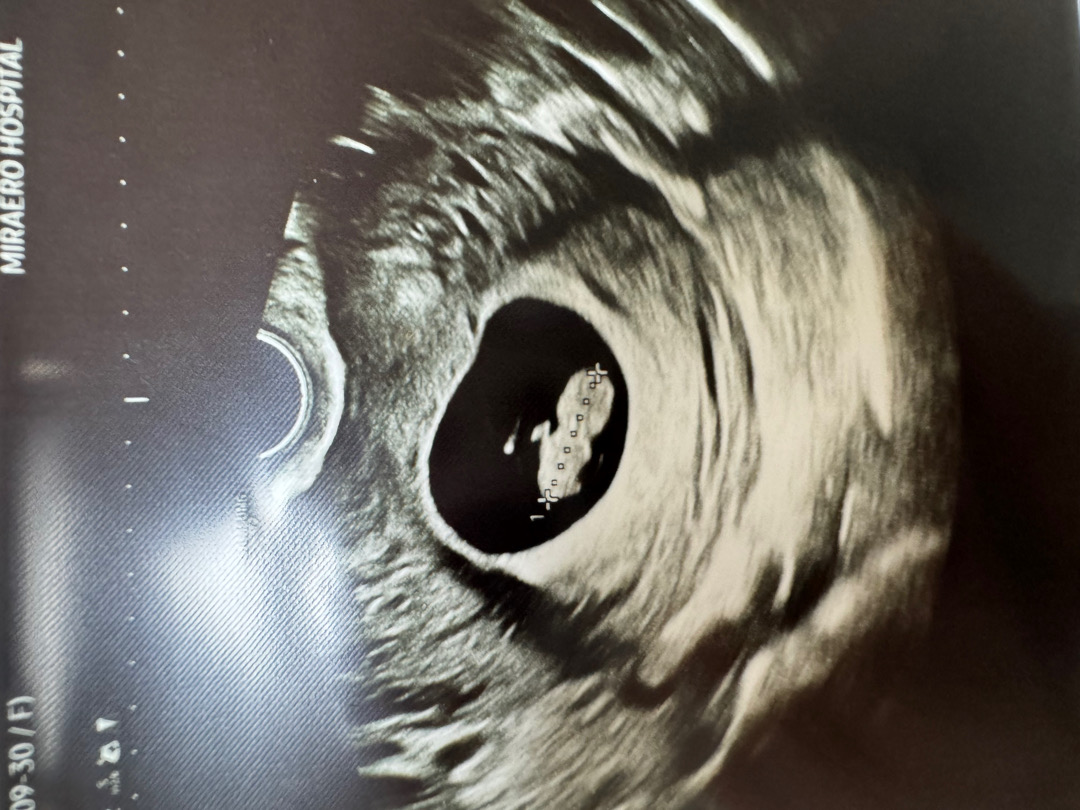

7주4일차 드디어 젤리곰 만났어요

2주만에 촘파봤는데 1.6cm 젤리곰만났어요 심장소리 165bpm 엄청 우렁차죠??ㅋㅋㅋㅋ 팔다리까지 보니까 너무 귀여워용 ㅜㅜ 이주동안 갈색혈나와서 걱정했는데 피고임없이 건강하게 잘 크고 있었더라구요ㅋㅋ 이제 무리한걱정은 안해야겠어용!! 한달 뒤 정밀촘파 예약했는데 얼른 시간이 가면 좋겠네용 ㅋㅋㅋㅋ